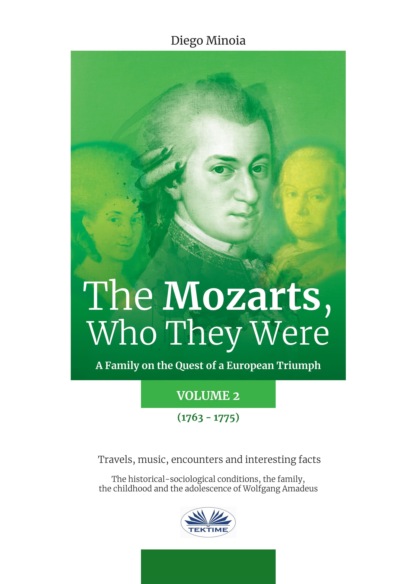

Внутриротовой доступ: при полуоткрытом рте зубоврачебным зеркалом отводят в сторону щеку, обеспечивая достаточный обзор свода преддверия рта и натяжение слизистой оболочки переходной складки в области моляров. Иглу вкалывают в слизистую оболочку выше проекции верхушек зубов на уровне второго-третьего моляров, а при их отсутствии – позади скулоальвеолярного гребня, вводя ее под углом 45° и продвигая вверх, назад и внутрь. При этом нужно следить за тем, чтобы игла все время скользила скошенной поверхностью острия по кости. По ходу продвижения иглы следует медленно выпускать раствор анестетика, предупреждая тем самым повреждение кровеносных сосудов крыловидного сплетения. Продвигая иглу на глубину 2 – 2,5 см, депонируют раствор анестезирующего вещества, чем достигается обезболивание области моляров, прилежащих к ним со стороны преддверия рта слизистой оболочки и надкостницы, а также задненаружной костной стенки верхнечелюстной пазухи (рис. 1.1, а). Внеротовой доступ: проколов кожу у передненижнего угла скуловой кости, направляют иглу под углом 45° вверх и внутрь к бугру верхней челюсти, доводя ее до кости; после чего депонируют раствор анестетика. Время наступления анестезии в зоне обезболивания такое же, как и при анестезии внутриротовым доступом (см. рис. 1.1, б).

Рис. 1.1. Анестезия на бугре верхней челюсти:

а – внутриротовой доступ; б – внеротовой доступ